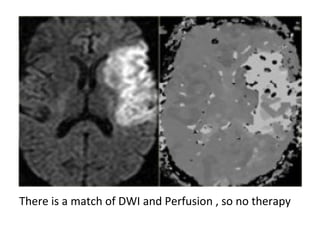

-Matched diffusion and perfusion abnormalities

correlate with the region of infarction and are

indicative of permanent neuronal death

On the DWI there is a large area with restricted diffusion in the

territory of the right MCA , notice also the involvement of the basal

ganglia , there is a perfect match with the perfusion images so this

patient should not undergo any form of thrombolytic therapy

There is a match of DWI and Perfusion , so no therapy